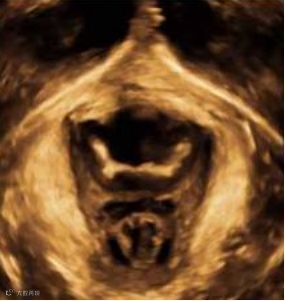

(超声下显示盆底肌群)

盆底超声的意义:可在患者出现临床症状前,发现盆底结构形态的变化,进行尿道周围性病变(尿道钙化、囊肿、憩室)、膀胱膨出、子宫脱垂、直肠膨出、肠疝及肛提肌和肛门括约肌损伤等盆底疾病的早期诊断。结合盆底肌超声检查及早的发现盆底功能障碍性疾病,能为妇产、泌尿系、盆底康复等相关学科的诊断治疗提供简便、实用、准确的诊断。